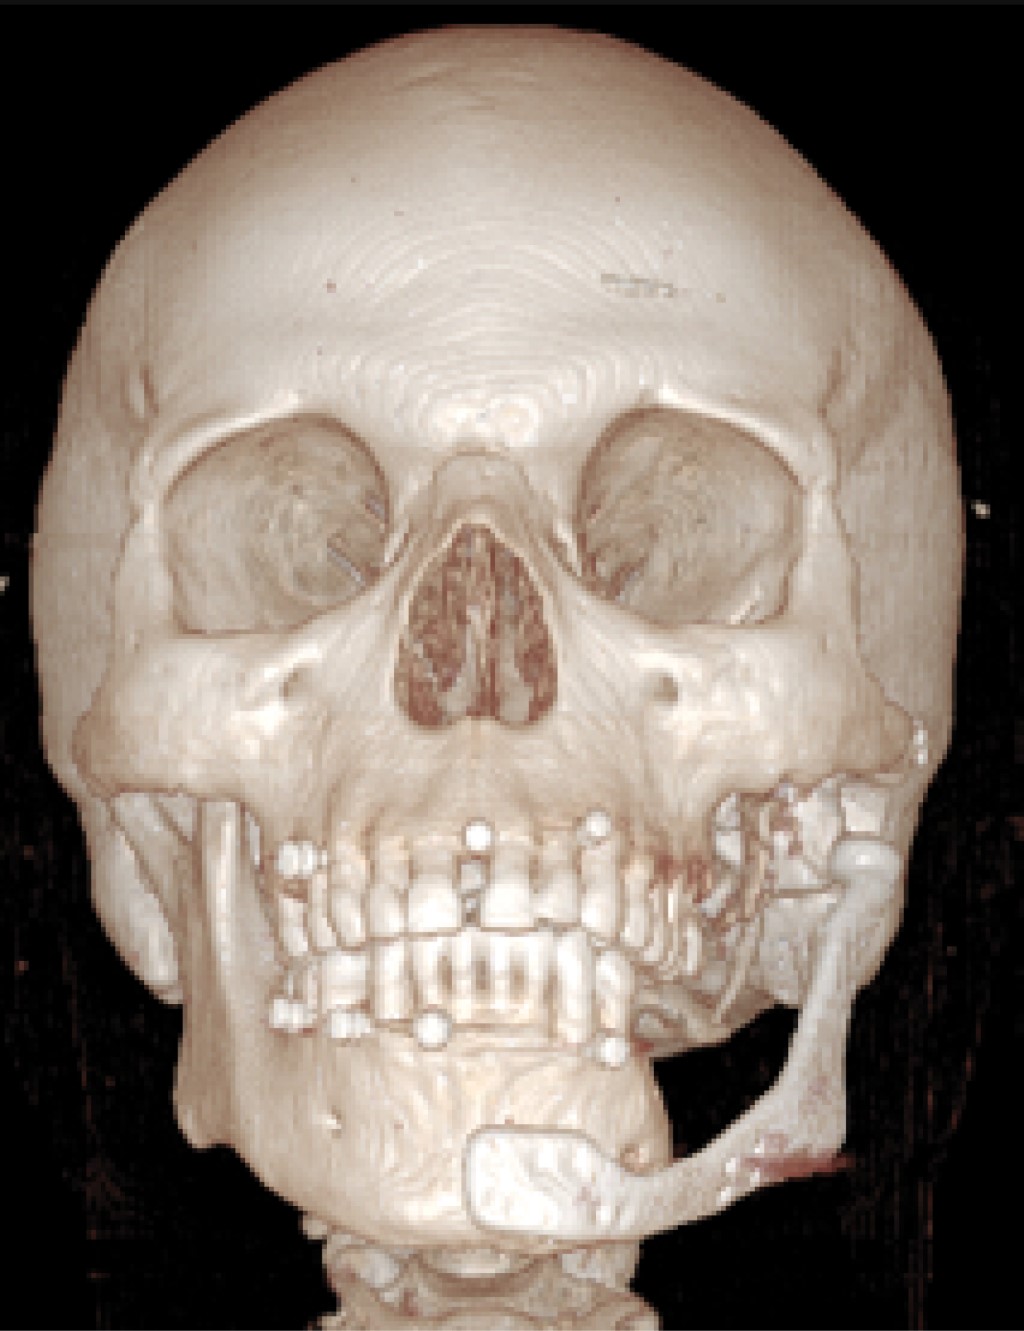

En agosto de 2015 se planificó la reconstrucción simultánea del componente mandibular y articular (Figura 5). A partir de este diseño se confeccionó una prótesis aloplástica personalizada Lorenz-Biomet (Biomet Microfixation, Jacksonville, FL, USA).

En conjunto con el servicio de endocrinología e infectología se preparó sistémicamente al paciente y en octubre de 2015 se realizó la cirugía reconstructiva, en la cual mediante un abordaje submandibular se insertó el componente mandibular y condilar, el cual fue fijado al cabo distal mandibular (Figura 6). Se realizó un segundo abordaje preauricular modificado a través del cual se insertó el componente correspondiente a la fosa glenoidea (Figura 7). Se recubrió el componente articular con una membrana de plasma rico en fibrina.

El postoperatorio transcurrió sin intercurrencias y se hicieron controles anuales (Figura 8). En el último control realizado en marzo de 2020 el paciente se presentó sin dolor, con una apertura bucal máxima de 40 mm, y buena dinámica mandibular con una laterodesviación hacia el lado izquierdo de 7 mm. Se observó una correcta estética y simetría facial (Figuras 9 y 10).

Figura 8

Figura 9

Figura 10